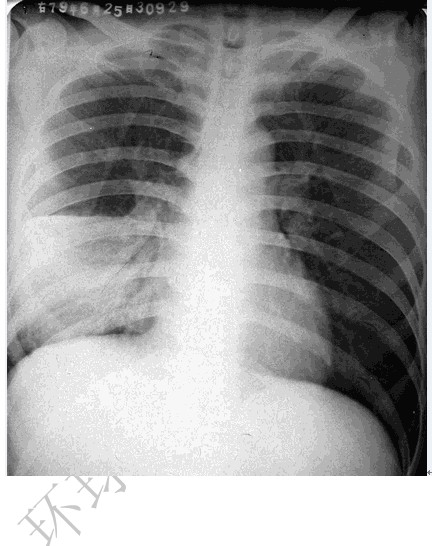

大葉性肺炎

圖示為右肺中葉大葉性肺炎

(1)胸部正位